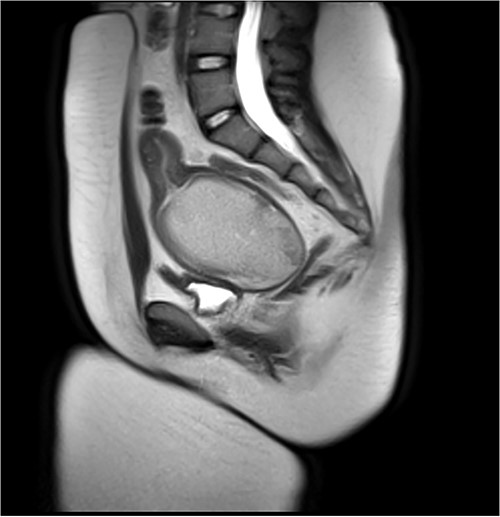

Attempt was made to perform US-guided drainage in IR using largest bore drain (12F) but the HMC had organized into a large clot and was too thick for drainage. Four mg of TPA was then injected into the HMC to allow breakdown of the clot, after which 300 ml of blood was successfully drained (Fig. 2).

Pre-vaginoplasty MRI- Image was taken after IR drainage and suppression to allow distension pre-vaginoplasty.